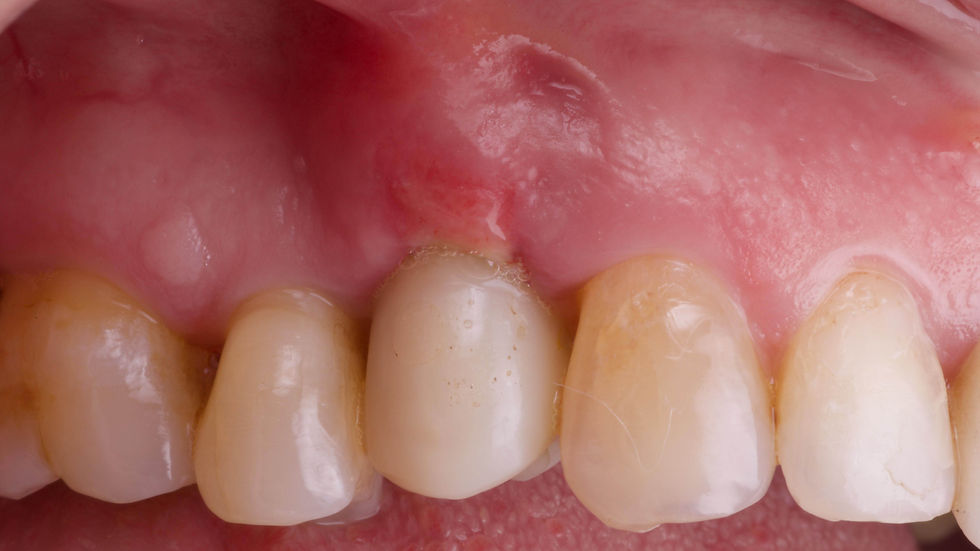

Vestibular tissue augmentation at 10 days: granulation tissue is still present in the area.